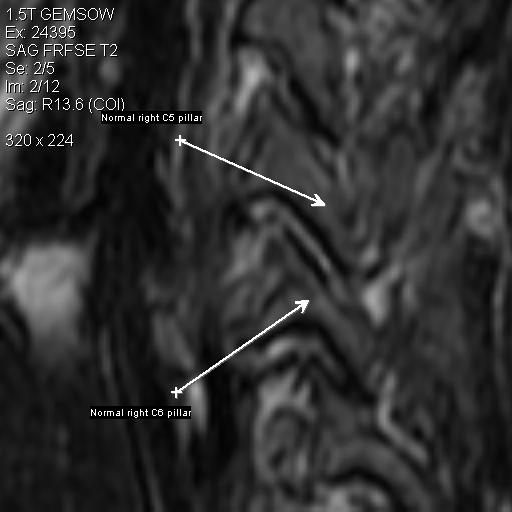

This shows the normal alignment of the C5-C6 facet joint on the right side. I've included this so you have a normal baseline for visual reference.